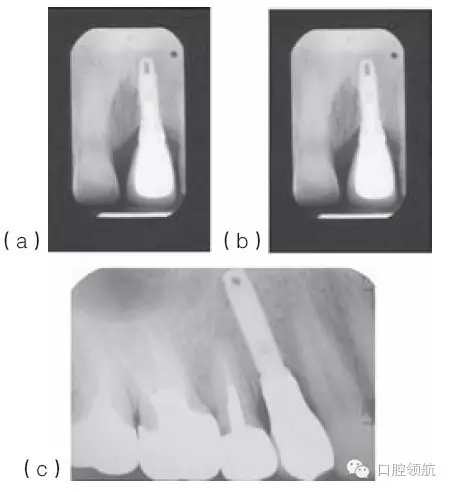

種植體適當(dāng)?shù)那蓄i/ 頸向位置,有利于建立逐漸過渡的外形和正常的穿齦形態(tài)。種植體切頸/牙合頸向的定位,很大程度上取決于現(xiàn)存骨的位置(圖10.33a~c),以及滿足美學(xué)需求的頸部過渡形態(tài)。因為種植體的平臺接口為小直徑的圓形,而齦緣的修復(fù)體截面為直徑較大的不規(guī)則幾何形態(tài),中間需要一定的過渡才能滿足美學(xué)的需求。一般來說,種植體植入到鄰牙釉牙骨質(zhì)界稍下方,以使所需的形態(tài)學(xué)改變逐步發(fā)生(圖10.34)。

圖10.33 (a)金屬烤瓷冠粘結(jié)后的根尖片。(b)種植體位于鄰牙釉牙骨質(zhì)界根方3mm的根尖片。切嵴到種植體頂部的距離太大,導(dǎo)致種植體金屬部件可能承受較大的力。(c)種植體植入到嚴重骨吸收的上頜第一前磨牙區(qū)。種植體到面的距離幾乎等于種植體的長度。

當(dāng)鄰間隙的骨高度良好,隨著時間的推移,軟組織可充填小的間隙(圖10.35a,b)。很顯然,軟組織頂部到骨之間的距離,對于維持天然牙和種植體之間的牙齦乳頭是很重要的。一項研究報道,在26名患者的上頜前牙區(qū),植入27顆單個種植體,對52個牙齦乳頭進行評估,來研究鄰間區(qū)牙槽嵴高度對種植體和天然牙之間牙齦乳頭的維持作用。研究發(fā)現(xiàn),種植體冠與天然牙鄰面觸點,到鄰面牙槽嵴頂?shù)木嚯x≤5mm時,牙齦乳頭100%存在。而當(dāng)這個距離≥6mm時,僅有50%的牙齦乳頭存在。

圖10.35 (a)上頜中切牙周圍的牙齦乳頭充填,形成了良好的軟組織外觀。(b)(a)圖中種植體冠的X線片顯示,相對修復(fù)體和種植體來說,鄰面牙槽骨處于理想的位置。(c)下頜種植支持式的局部固定義齒,采用牙齦色的烤瓷來改善頸部外觀。(d)復(fù)制的上頜全口義齒的前面觀,一側(cè)的頰側(cè)翼板被去除,以模擬上頜全口固定義齒的外觀。(e)右側(cè)觀唇部的支撐效果。(f)左側(cè)觀唇部的支撐效果。這一側(cè)對唇部的支撐明顯不如對側(cè)。